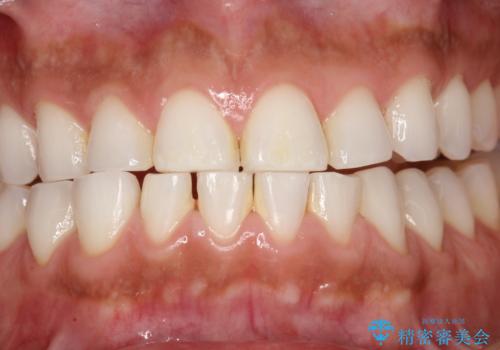

PMTCでお口のメンテナンス

- 痛みや特に気になるところはないが、しっかりとクリーニングしてほしいとのことで来院された患者様です。PMTC 30分コースでのメンテナンスを行いました。

歯を長持ちさせるために、1番の対策が、PMTC を定期的に行うことです。虫歯や歯周病の予防・再発の予防などと、患者様の歯の健康を保つためプロフェッショナルクリーニングを行っています。

痛みや症状が無くても、歯科医院にて専門的なクリーニングを行うことが大切です。